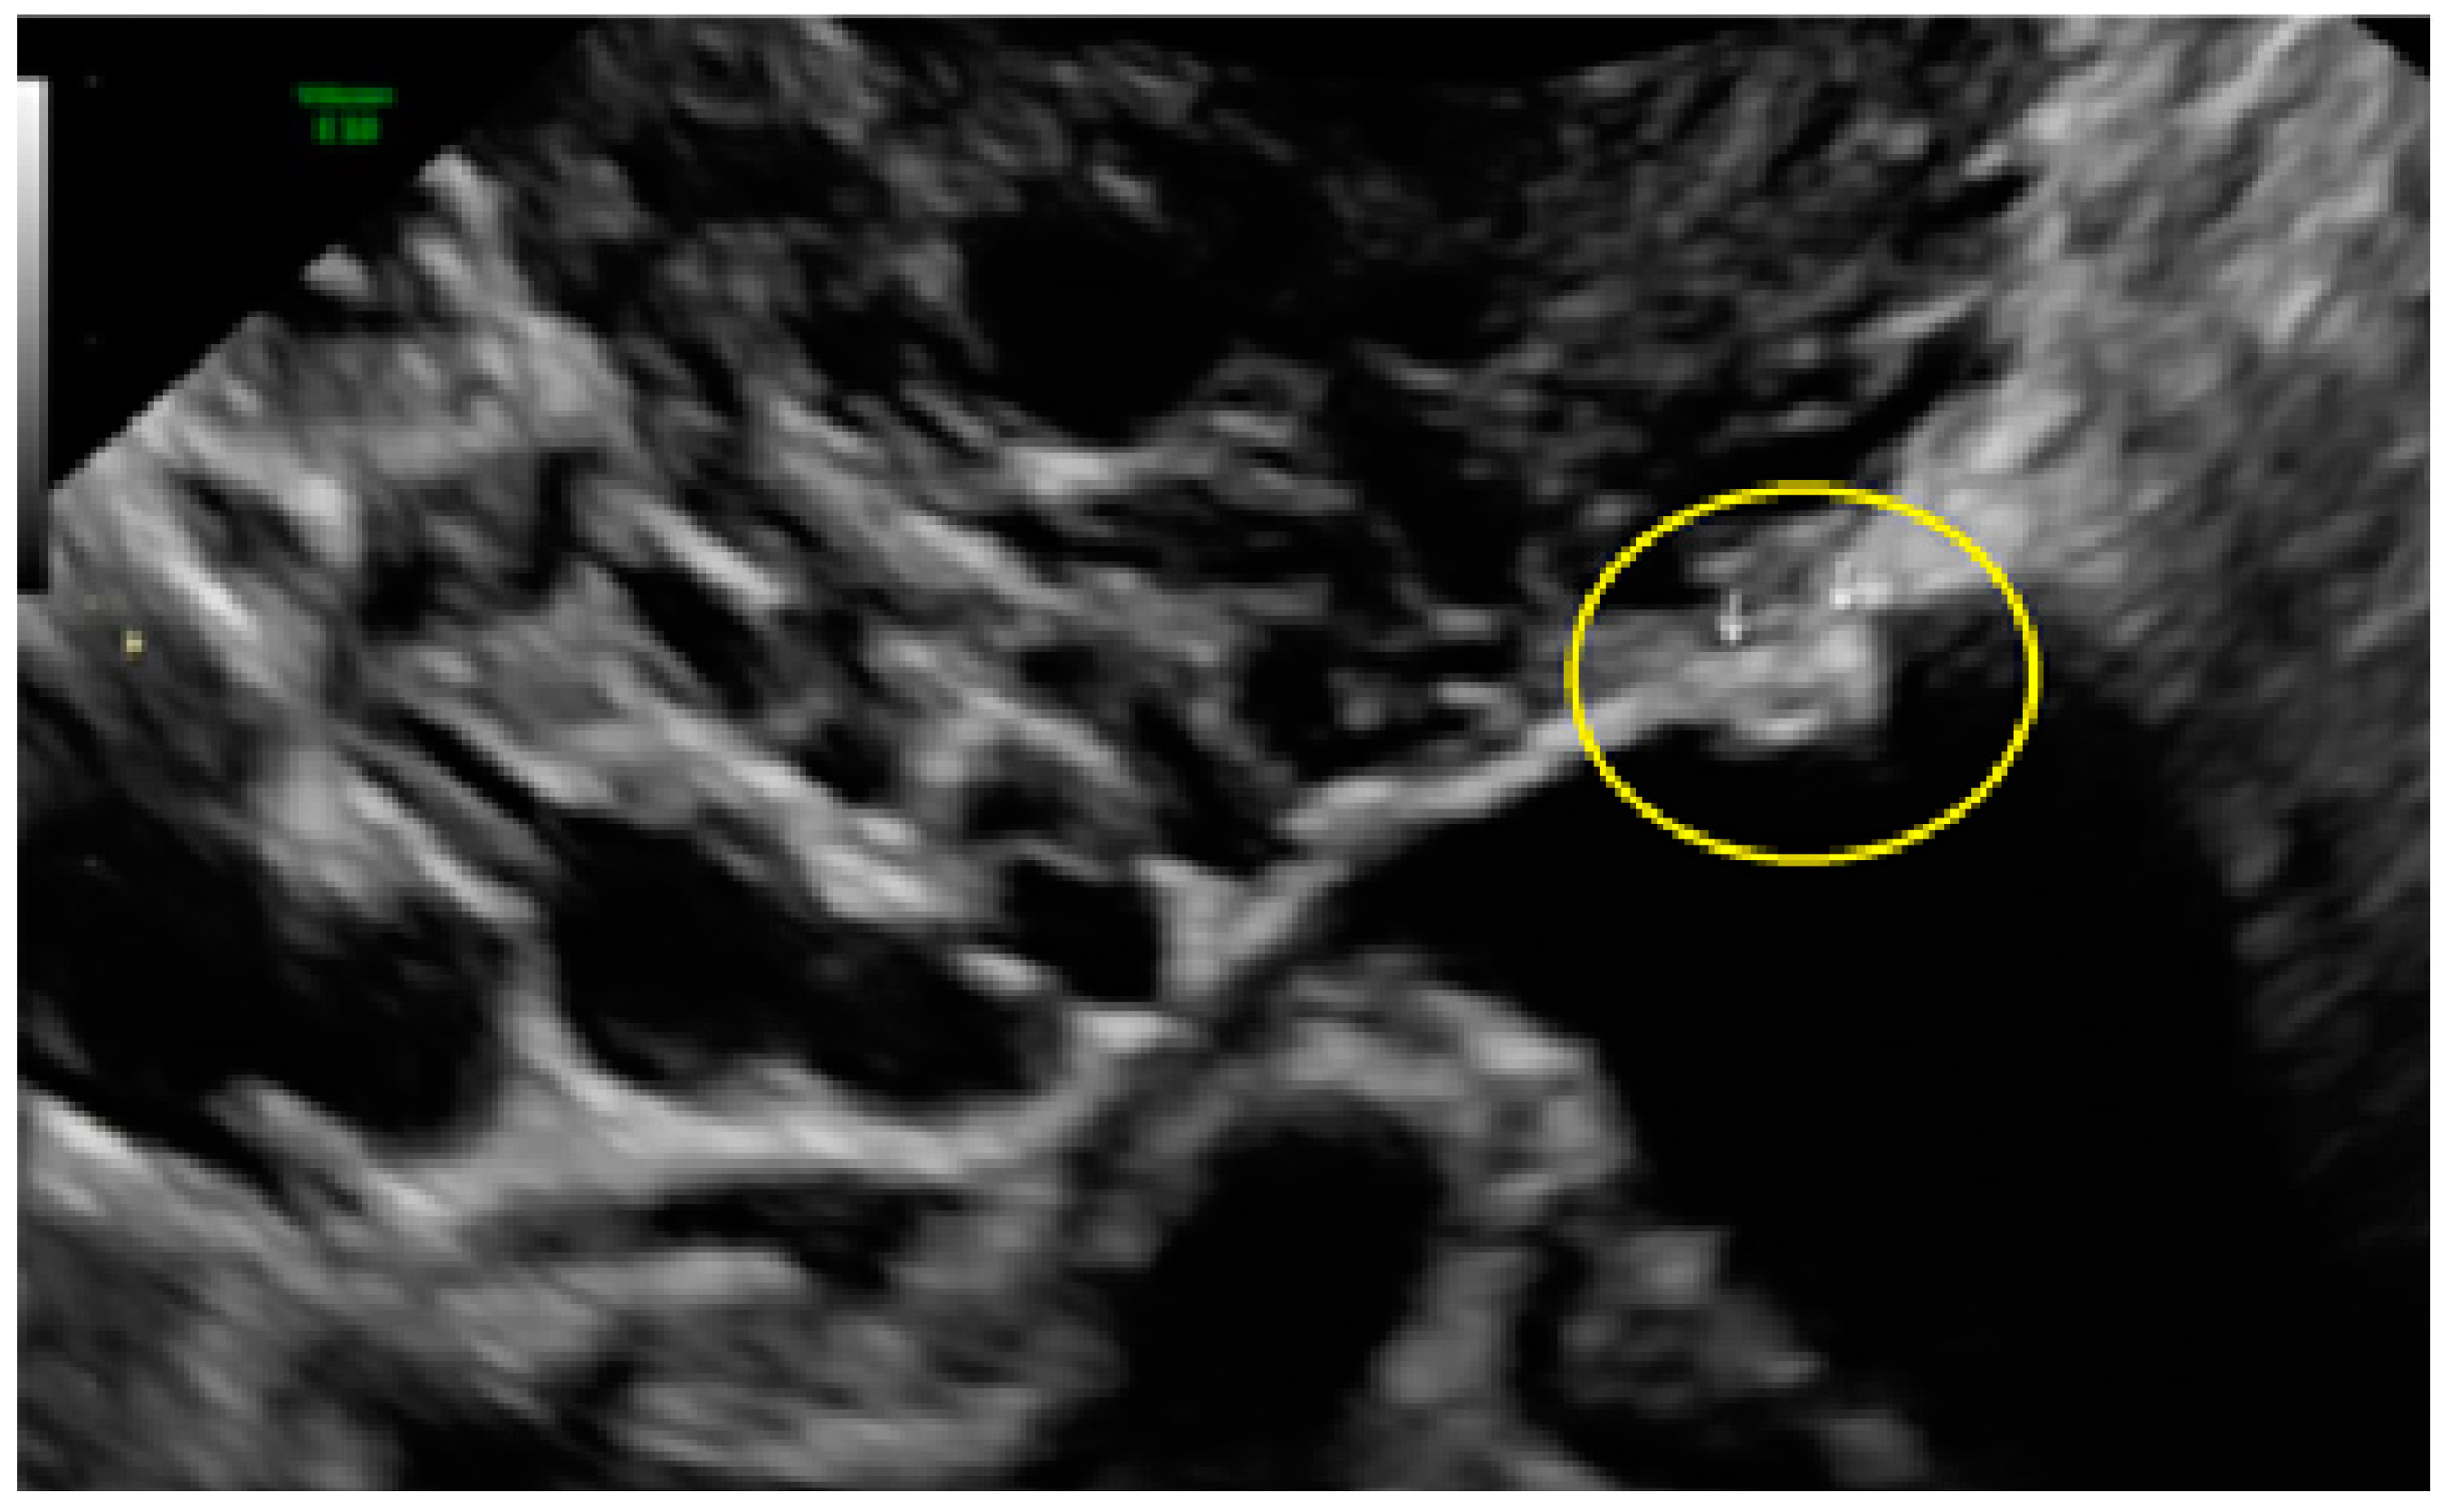

- The presence of hyperechoic foci (we called this a “pearl”).

- The presence of velamentous (filmy) adhesions associated to the lesion (we called this a “veil”).